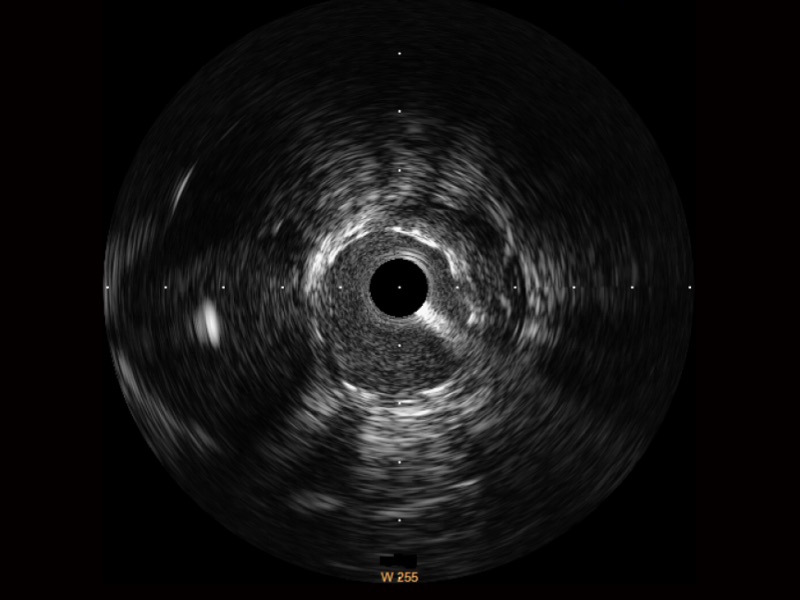

• 竞技宝(JJB)官方网站宽频IVUS图像

• 传统IVUS图像

对比传统IVUS导管成像,竞技宝(JJB)官方网站宽频IVUS图像的近场支架梁显影更细腻,远场中膜外血管仍清晰可辨,兼顾远中近,兼顾分辨力与穿透深度